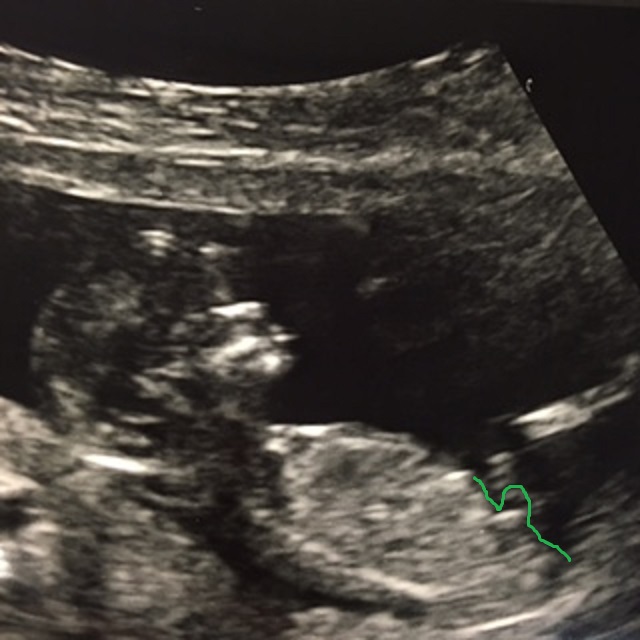

12 weeks 4 days...Does this look boyish??

So in real life the picture below doesn't show a nub, which is why I didn't include it before. It honestly looks like a blurry image, part of the leg or cord, but when I took a picture of the picture using my phone and filters there appears to be a shape of a nub and it looks boyish to me. Please let me know your thoughts and if you think this actually is the nub even though you can't really see it in the hard copy of the picture.

Attachment 32813